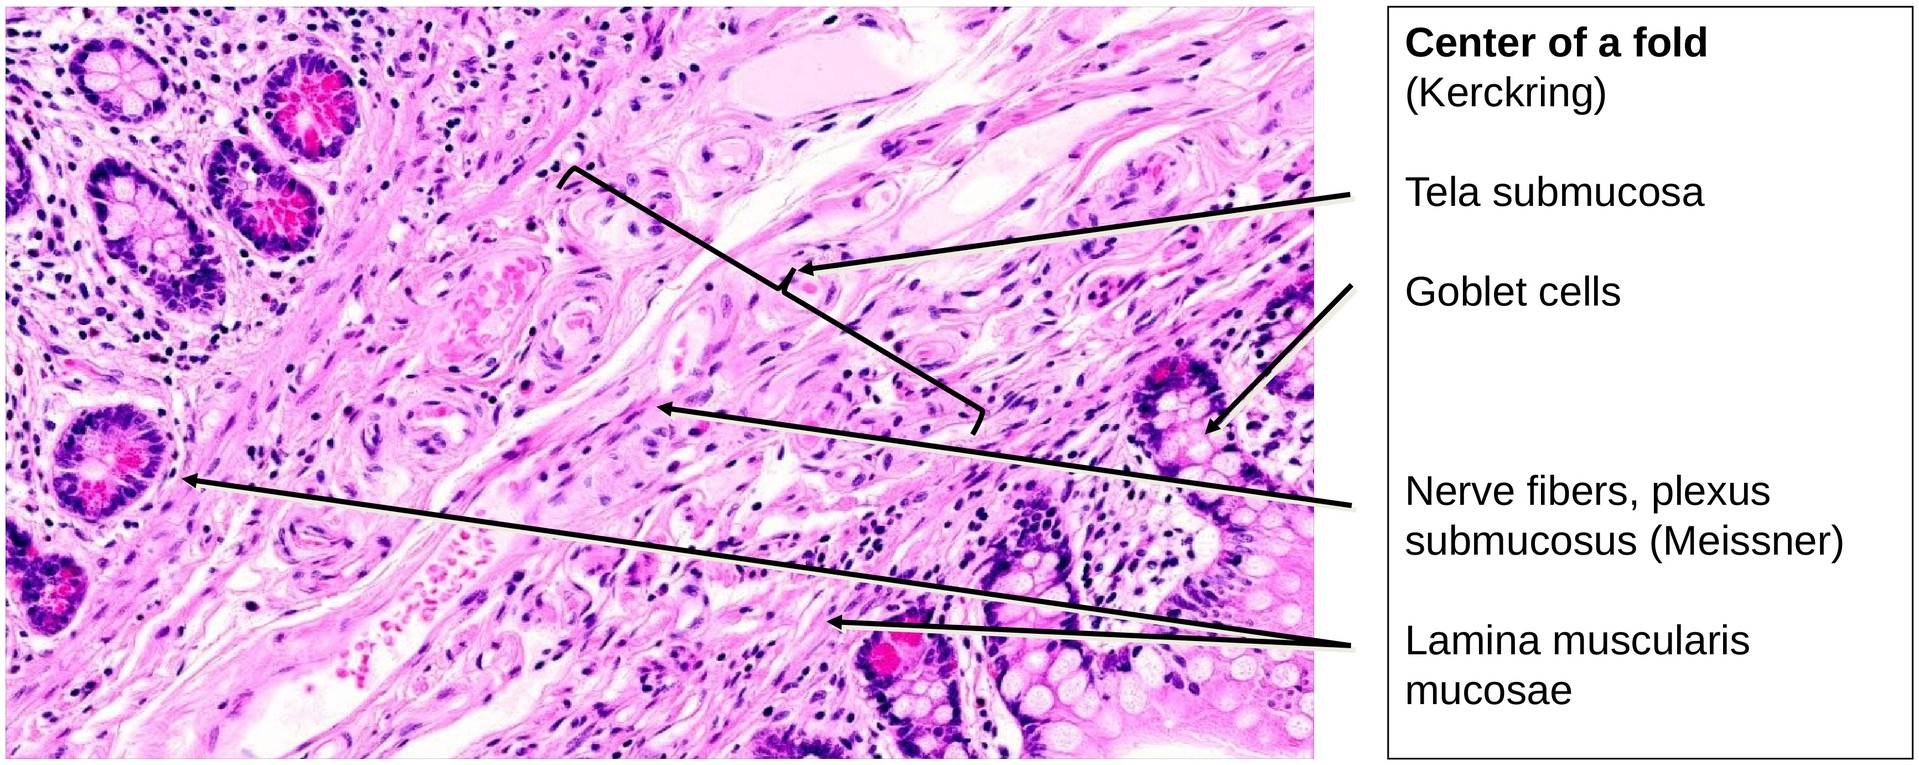

The general layered organization of the GIT wall is well preserved: - Tunica mucosa (with lamina epithelialis, lamina propria, and lamina muscularis mucosae). - The muscularis mucosae is relatively thin but extends into the circular folds and occasionally into the villi. - Tela submucosa, which appears robust but shows few identifiable elements of the submucosal plexus (Meissner’s plexus). - Tunica muscularis, composed of: - An inner circular layer (particularly prominent here). - An outer longitudinal layer, between which the myenteric plexus (Auerbach’s plexus) is clearly visible, containing ganglion cells and nerve fibers.

The epithelium of the villi shows numerous goblet cells, interspersed among the enterocytes bearing a distinct brush border. Between the villi, short intestinal crypts (crypts of Lieberkühn) extend into the lamina propria.

- Search for elements of the submucosal (Meissner’s) plexus within the submucosa.